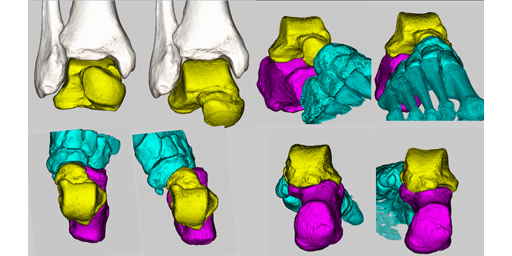

三次元で考える足部・足関節CT~複雑な関節形態を“再現する”工夫~